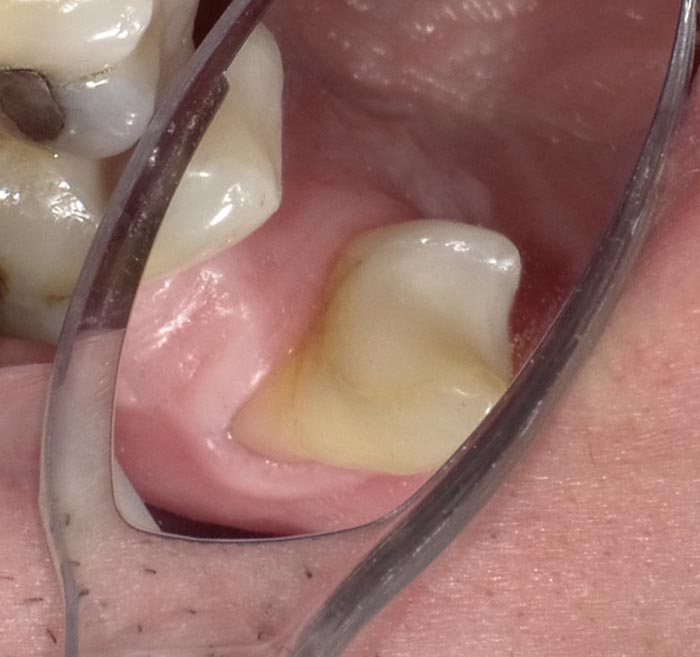

A 37-year-old patient presented for treatment after years of neglect. After administering anesthetic and placing an Isolite isolation device, we prepared teeth #10–12 and restored them

with Activa Bioactive-Restorative composite.

• Figure 4